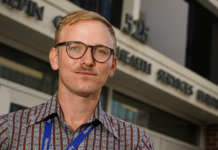

Meet Joe Biden’s Monkeypox Czar — A Gay Doctor In Drag Who Wants To...

Dr. Demetre Daskalakis has a long history of working in public health on issues pertaining to the LGBT community, and now he’s helping lead the Biden administration’s response to the ongoing...

Meet Dr. Demetre Daskalakis, the CDC’s Out & Proud Health Expert – Out Magazine

Earlier this summer, Dr. Demetre Daskalakis was chosen by President Joe Biden as the White House's National Monkeypox Response Deputy Coordinator. Since then, Daskalakis has been leading the efforts to respond to...